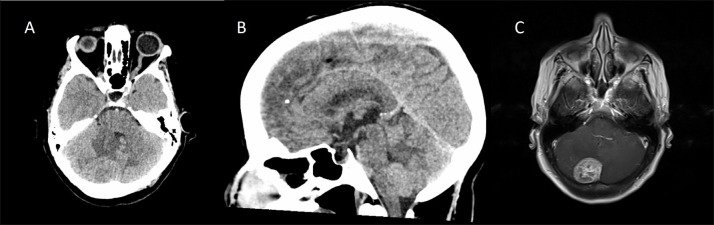

Abstract Image